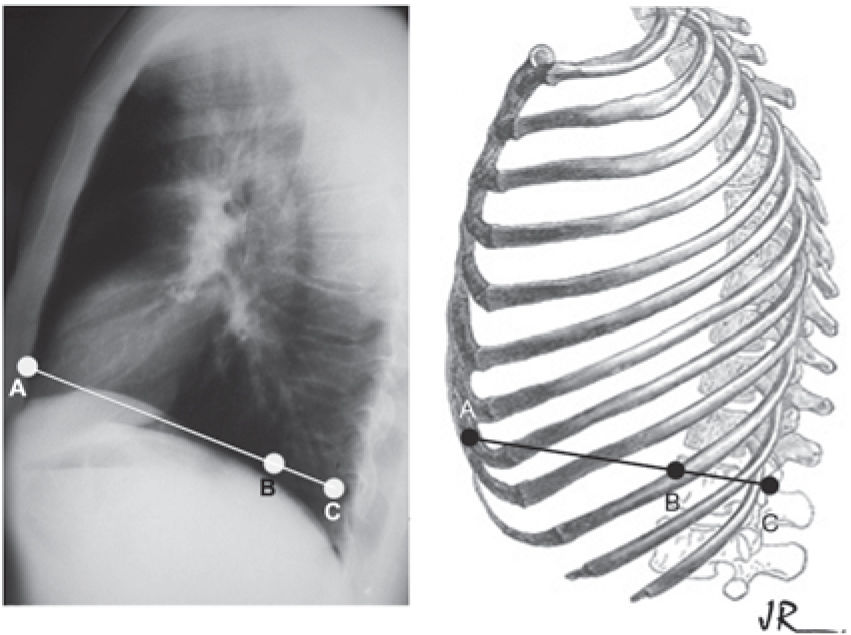

The A and B clinical measurements were carried out with the patient in a horizontal supine position on a flat table parallel to the floor during deep inhalation. (Figures 1, 2, and 3). The A measurement was defined as the largest anteroposterior diameter at the level of the distal third of the sternum, and the B measurement was the largest depth at the same level. The anthropometric index (AI)14 for PEX was defined as the B measurement divided by the A measurement (AI = B/A).

The radiographic measurements were obtained from the simple thorax radiography, where the BC measurement was equal to the sagittal diameter of the vertebra, and the AC measurement referred to the sagittal anteroposterior diameter of the posterior board of the sternum to the posterior portion of the vertebral body. The lower vertebral index (LVI)18 was defined as the ratio between BC and AC, (LVI = BC/AC) (Figure 4).